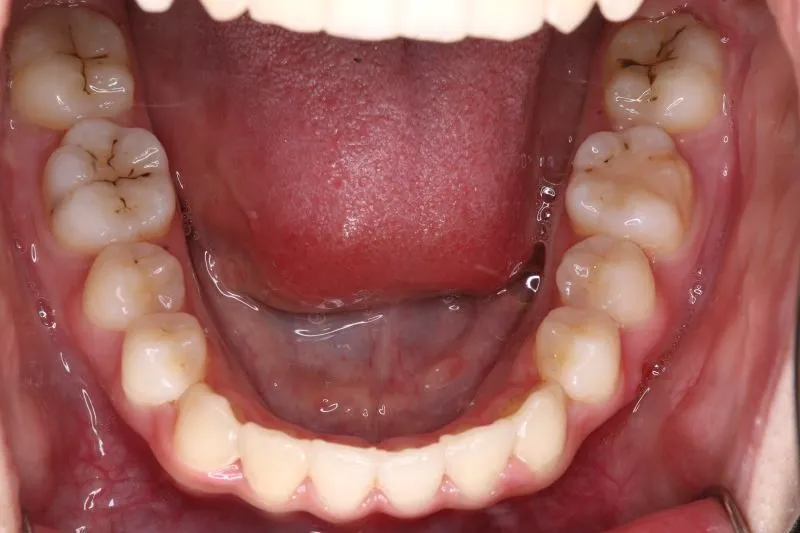

初診時年齢 高校生 (女性) 主訴 歯並びがガタガタ・口元の突出感

診断名 叢生・開咬・上下顎前突 装置名

特徴 ゆがんで生えている

状態 ガタガタ・でこぼこに生えている(叢生)

受け口(下顎前突/反対咬合)

前歯で噛めない(開咬/オープンバイト)

上下前歯、口元が出ている、口ゴボ(上下顎前突)

ガタガタの歯並びにお悩みの患者様でした。

口唇の突出感の他、下顎面高が長い印象も認められました。

歯科矯正アンカースクリューを用いた治療で、非抜歯で口唇突出の改善、臼歯の圧下、叢生の解消を図りました。

叢生は解消し、口元が大幅に引っ込み、下顎面高も縮小しました。